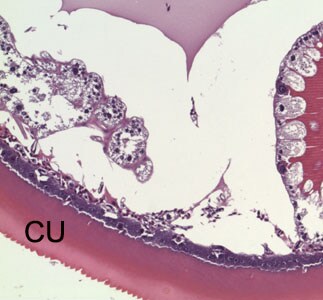

An 81-year-old man, with a previous history of basal-cell carcinoma on his upper right arm and shoulder, presented with a small protuberance in the hollow of his left knee. A biopsy specimen was collected, sectioned, and stained with hematoxylin-and-eosin (H&E). Figures A–D show what was observed by the attending pathologist. What is your diagnosis? Based on what criteria?

Figure D